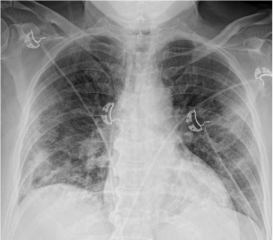

Методы лучевой диагностики применяют для выявления COVID-19 пневмоний, их осложнений, дифференциальной диагностики с другими заболеваниями легких, а также для определения степени выраженности и динамики изменений, оценки эффективности проводимой терапии.

К методам лучевой диагностики патологии ОГК пациентов с предполагаемой/установленной COVID-19 пневмонией относят:

- Обзорную рентгенографию легких (РГ),

Стандартная РГ имеет низкую чувствительность в выявлении начальных изменений в первые дни заболевания и не может применяться для ранней диагностики. Информативность РГ повышается с увеличением длительности течения пневмонии. Рентгенография с использованием передвижных (палатных) аппаратов является основным методом лучевой диагностики патологии ОГК в отделениях реанимации и интенсивной терапии (ОРИТ). Применение передвижного (палатного) аппарата оправдано и для проведения обычных РГ исследований в рентгеновском кабинете. В стационарных условиях относительным преимуществом РГ в сравнении с КТ являются большая пропускная способность. Метод позволяет уверенно выявлять тяжелые формы пневмоний и отек легких различной природы, которые требуют госпитализации, в том числе направления в ОРИТ.